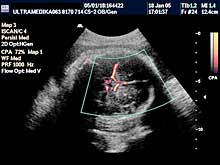

1. Arahnoidalne ciste ne bi trebalo da predstavljaju dijagnostički problem. One su avaskularne te se kolor Dopplerom (CD) ne dobija protok u njima. Ako postoji dilema koristi se kolor Power angio mod (CPA) (sl 010) koji registruje i protoke ekstremno malih brzina bez obzira na upadni ugao ultrazvučnog talasa u odnosu na krvni sud, što je osnovni preduslov za registrovanje protoka krvi, od pre 20 gidina poznatim konvencionalnim kolor Dopplerom . Mora se napomenuti da u toku pregleda u III trimestru trudnoće, jako često postoje nepovoljni uslovi za pregled (neadekvatan položaj ploda, neoptimalna količina plodove vode, debljina prednjeg trbušnog zida trudnice i položaj posteljice). U ovakvim situacijama aparati slabijih tehničkih mogućnosti, sa nižom cenom koštanja i posedovanjem klasičnog načina dobijanja ultrazvučne slike i kolor Doppler tehnike, imaju znatno ograničene dijagnostičke mogućnosti.